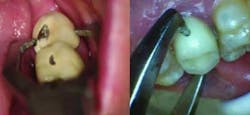

Fig. 1 — Dimple preparation on buccal surface of mandibular second molar PFM crown and palatal surface of maxillary second premolar PFM crown.

Fig. 2 — Dimples act as receptacles for beaks of Baade pliers.Once the dimples are made and the Baade pliers are in position (Fig. 3), the operator attempts to break the cement seal and remove the crown with a twisting motion of the hand and wrist. This technique works especially well on teeth with short clinical crowns and/or teeth that have been prepared with excessive taper. If the crown resists displacement using this technique, it is unwise to attempt to force the crown off with the Baade pliers, as the tooth may fracture. The dimple technique is also contraindicated on teeth with advanced loss of periodontal attachment, unfavorable crown-to-root ratio, or excessive mobility. In these cases, the crown should be sliced from the buccal gingival margin to the occlusal or incisal aspect and then pried off with a narrow-ended hand instrument.